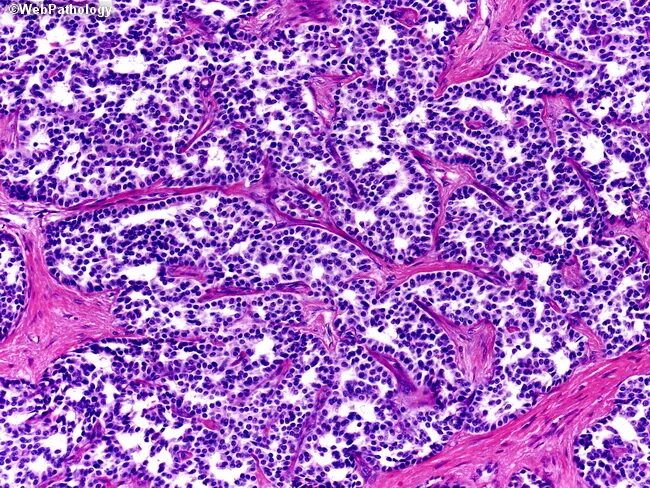

Гистология аденокарциномы